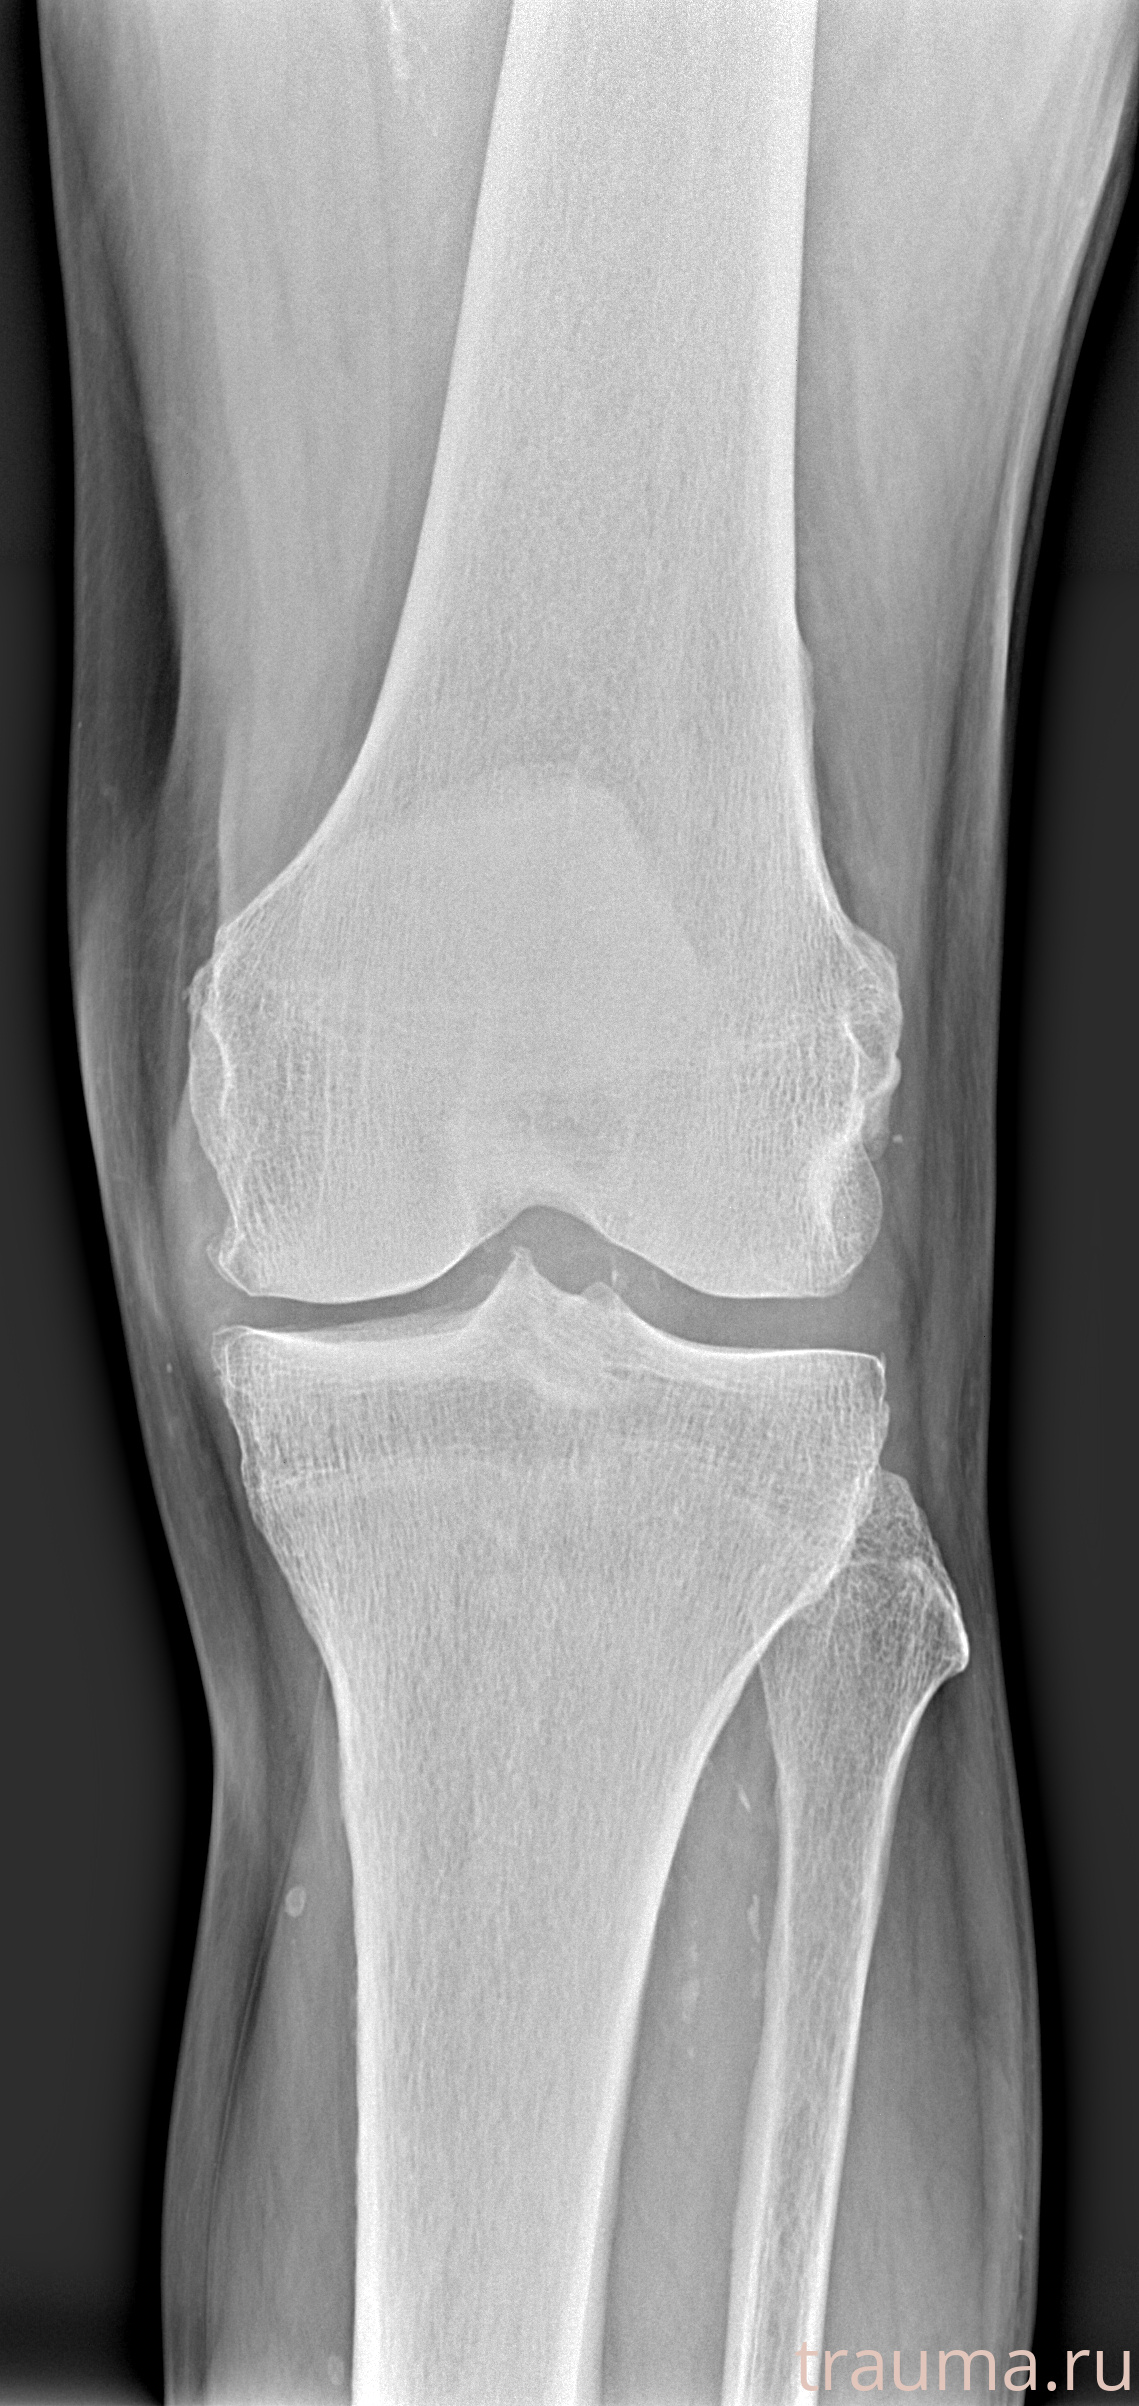

Рентгенограммы

Рентген на дому: по вашему адресу приезжает врач-рентгенолог, травматолог-ортопед с мобильным рентгеновским аппаратом, проводит диагностику травмы или заболевания, делает необходимые рентгенограммы, дает рекомендации по дальнейшему лечению. Получить качественные снимки в домашних условиях возможно благодаря уникальной методике, разработанной МосРентген Центром для института  Склифосовского